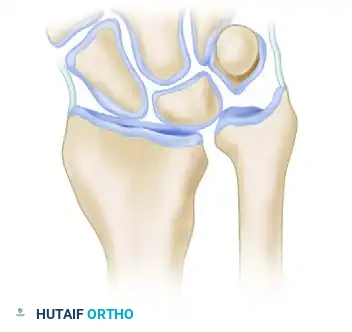

Distal radius malunion is a complex clinical entity that frequently results from the nonoperative management of displaced fractures or the secondary loss of reduction following initial stabilization. The resulting deformity—typically characterized by dorsal tilt, radial shortening, and loss of radial inclination—profoundly alters the biomechanics of the radiocarpal and distal radioulnar joints (DRUJ).

A dorsal tilt of the distal radius exceeding 20 degrees shifts the axial load transmission from the normal 80% radius / 20% ulna distribution to approximately 50% radius / 50% ulna. This exponential increase in ulnar load is the primary driver of ulnar-sided wrist pain and secondary triangular fibrocartilage complex (TFCC) pathology in malunited fractures.

* Re-establish the articular congruity and stability of the DRUJ.

7. Distal Radioulnar Joint (DRUJ) Assessment

Following rigid fixation of the radius, the tourniquet is deflated, and hemostasis is achieved. The DRUJ must now be dynamically assessed through a full range of pronation and supination.

If normal ulnar variance cannot be fully restored through the radial osteotomy alone, or if the DRUJ remains tight and incongruent, a concomitant ulnar shortening osteotomy must be performed to decompress the ulnocarpal joint and restore DRUJ kinematics.

- Persistent DRUJ Instability: Failure to recognize and address concomitant TFCC tears or residual ulnar positive variance will result in persistent ulnar-sided wrist pain despite a healed radial osteotomy.